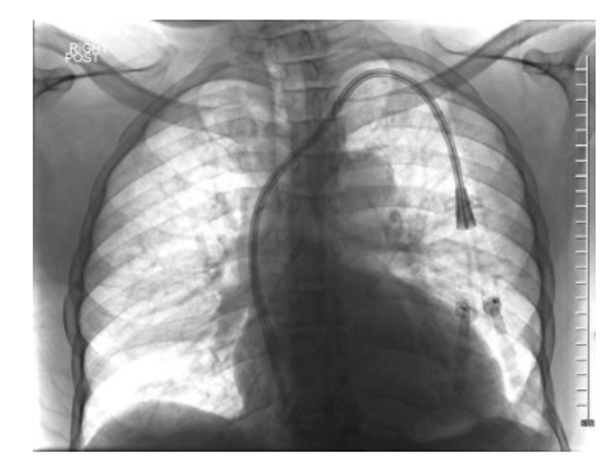

What tool would be the best choice to embolize this pulmonary avm?

vascular plug

Rule 1 of embolics: don’t be dangerous. Clear, large caliber right to left shunt here, so liquids and particles are no good (this is a different scenario than chronic lung disease with bronchial shunting, for which large particles are acceptable). Here, even coils are nerve wracking as they could slip right through, though are definitely an acceptable answer. The vascular plugs are a nice option here as migration risks are lower.